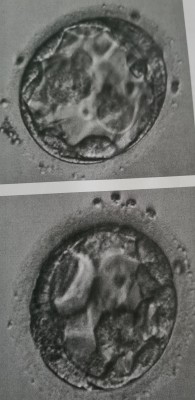

Laut KiWu ist die obere eine expandierende Blastocyste und die untere wurde als einfache Blastocyste eingestuft.

beide BCs haben für Tag5 einen guten Expandierungsgrad erreicht und die Strukturen sind zeitgerecht ausgebildet.

Bei der unteren BC ist die Zona noch relativ dick, so dass die Anwendung des assisted hatchings empfehlenswert war.

Ich würde beide mit 3BB einstufen d.h. die Chancen sind sehr gut.